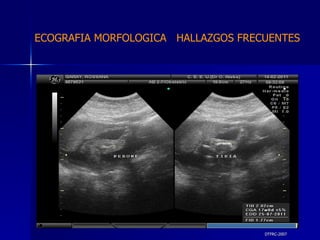

DTFRC-2007 ECOGRAFIA MORFOLOGICA  HALLAZGOS FRECUENTES   MATERIAL Y METODO ES UN ESTUDIO DESCRIPTIVO, RETROSPECTIVO  DE ESTUDIO ECOGRA FICOS REALIZADOS ENTRE MARZO 07 A MARZO 08 EQUIPO DE ALTA RESOLUCION   VOLUSON 730 PRO  MEDISON SA 8000 live MEDISON SA 8000SE CRITERIO DE INCLUSION:   POBLACION GENERAL    GESTACIONES  20 a 24 SEMANAS   UNIVERSO  N 211

DTFRC-2007 ECOGRAFIA MORFOLOGICA  HALLAZGOS FRECUENTES   GENITOURINARIA DISPLASIA RENAL MULTIQUISTICA  3 HIDRONEFROSIS  2 QUISTE DE OVARIO FETAL  1 SISTEMA DIGESTIVO DILATACION INTESTINAL  2  SISTEMA ESQUELETICO   PIE BOT  2  20 % 6 % 6 %

DTFRC-2007 ECOGRAFIA MORFOLOGICA  HALLAZGOS FRECUENTES   OTROS HIGROMA QUISTICO  2 ENFERMEDAD ADENOMATOSA PULMONAR  1 ARTERIA UMBILICAL UNICA  2 HIDROPS FETAL NO INMUNE  1 QUISTE DE CORDON UMBILICAL  1 ALTERACION DE LIQUIDO ANMIOTICO  2 SINDROME TRAFUSIONAL FETO FETAL 1 LABIO LEPORINO  2 TOTAL  12  42 %